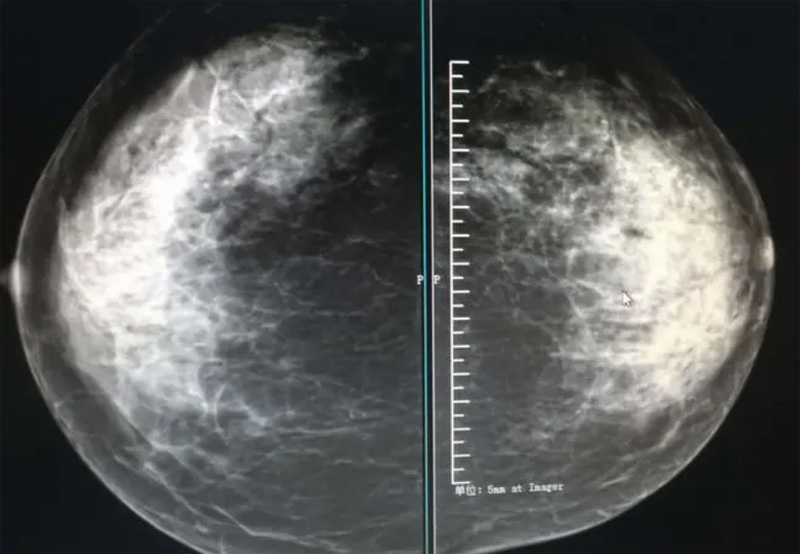

乳腺DR攝影體位有頭尾位及內(nèi)外側(cè)斜位,

乳房在片子的中央,乳頭切線位,可見小部分胸大肌,內(nèi)側(cè)乳腺組織應(yīng)全部包括在片中,外側(cè)乳腺組織盡可能包括在片中。一張好的MLO位圖像顯示如下:乳房被推向前上,乳腺實質(zhì)充分展開,胸大肌可見,較松弛,下緣達(dá)到乳頭水平,乳頭在切線位,部分腹壁包括在片中,但與下部乳腺分開,絕大部分乳腺實質(zhì)顯示在片中。乳腺組織外緣可見乳頭的輪廓;乳腺后方的脂肪組織被很好地顯示出來,乳房無皺褶。對于CC位及MLO位顯示不良或未包全的乳腺實質(zhì),可以根據(jù)病灶位置的不同選擇以下體位:外內(nèi)側(cè)位(LM)、內(nèi)外側(cè)位(ML)、內(nèi)側(cè)頭尾軸位(MCC)、外側(cè)頭尾軸位(LCC),尾葉位(CLEO)及乳溝位。在臨床實踐中,對于常規(guī)體位上發(fā)現(xiàn)的異常改變,可以進(jìn)一步采取一些特殊的攝影技術(shù),包括局部加壓攝影、放大攝影或局部加壓放大攝影技術(shù)。